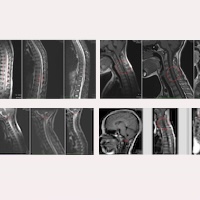

Sur ses images d’IRM préopératoires de 2017 (Fig.1), on pouvait observer, entre autres constatations :

Dans ce cas, on peut également observer sur les images d’IRM une amélioration progressive de l’état de la patiente après l’intervention, comme le montrent les Figures 2, 3 et 4.

Ici, nous présentons comme première image de chaque comparaison de contrôle, les IRM de 2019, qui étaient encore inchangées par rapport aux préopératoires de 2017 — dans la plupart des cas, il faut attendre quelques années avant de pouvoir observer des améliorations sur les images.

C’est à partir des IRM de contrôle de 2023, cinq ans après l’intervention, que nous avons la preuve d’une amélioration évidente visible sur chacune des images, encore plus marquée lors du dernier contrôle, fin 2024, à sept ans, avec :

–    L’ascension des amygdales cérébelleuses et la normalisation du    quatrième ventricule (Fig. 2).